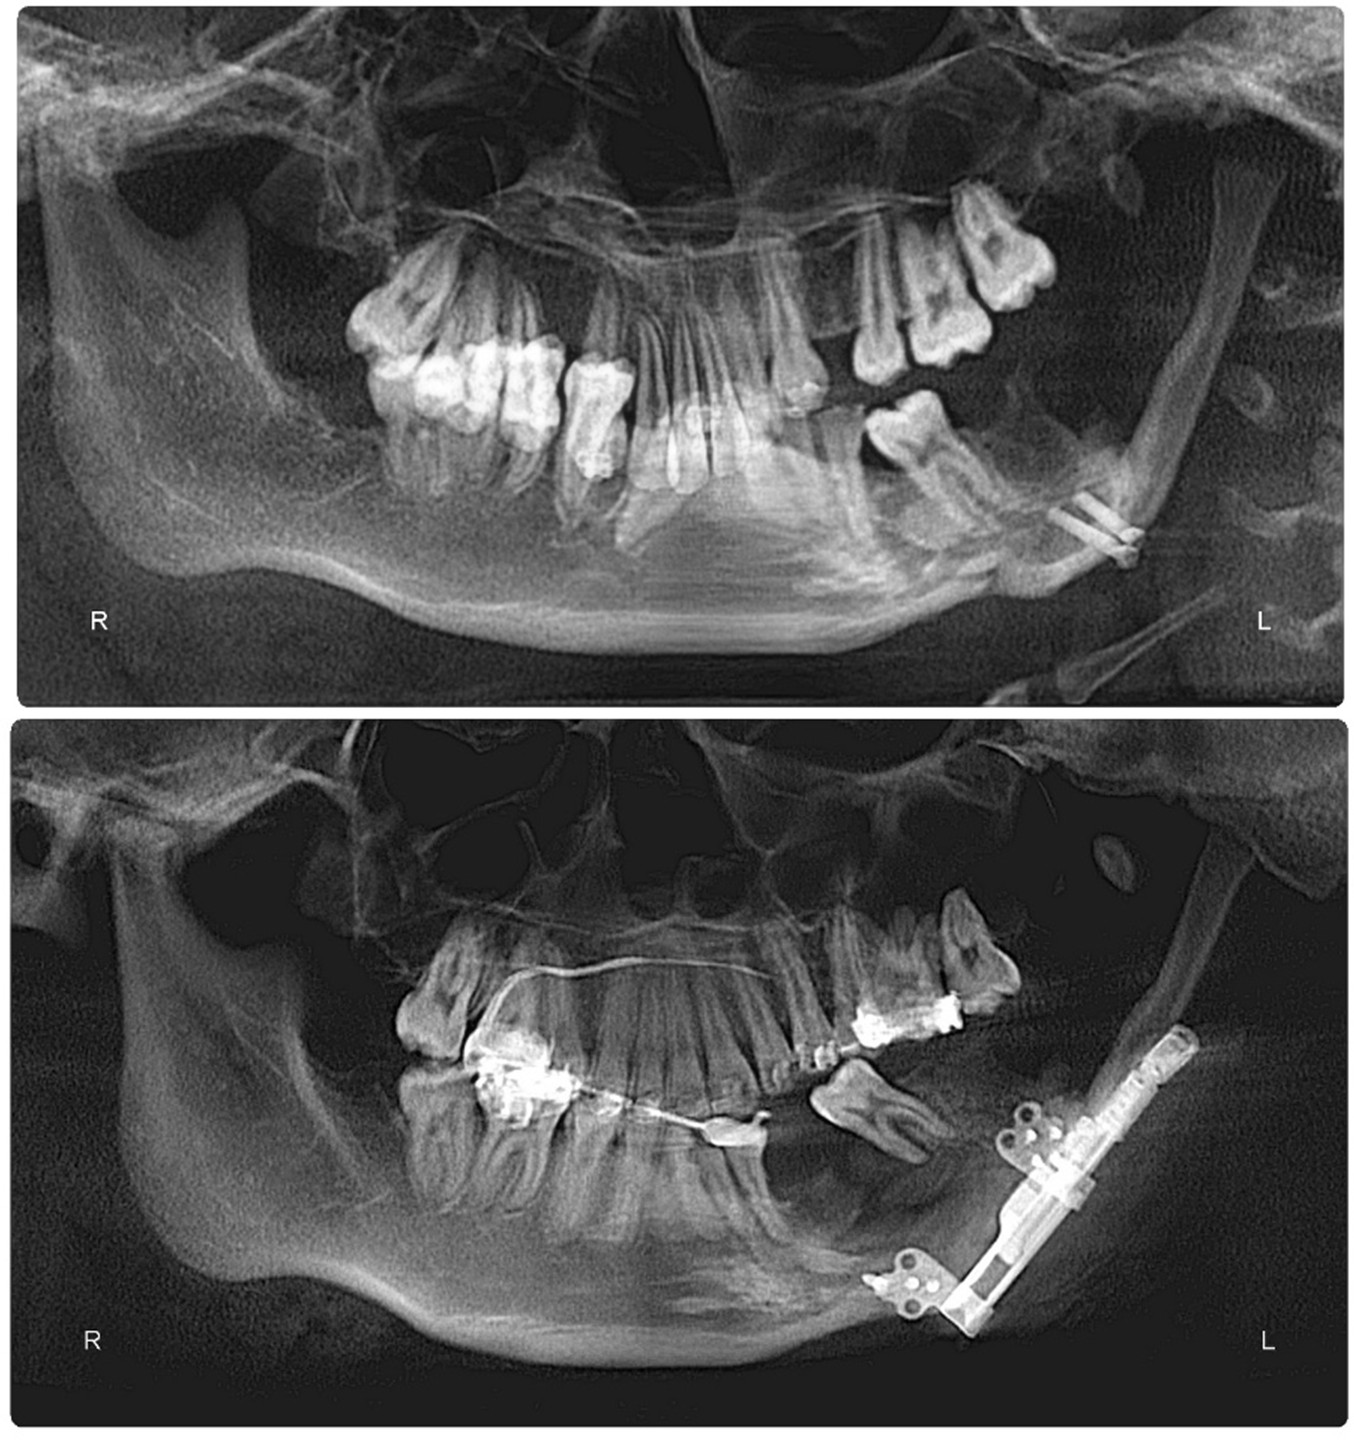

Craniofacial Orthodontics represents one of the most advanced and specialized fields within orthodontics. This highly focused area involves the treatment of patients with congenital or acquired craniofacial conditions such as cleft lip and palate, craniosynostosis, Hemifacial Microsomia, and other complex facial anomalies. Craniofacial orthodontists work closely with Multidisciplinary Teams—including plastic surgeons, oral surgeons, pediatricians, and speech therapists—to coordinate care that not only improves function and appearance but transforms lives. The complexity of these cases demands exceptional clinical skill, in-depth anatomical knowledge, and a high level of precision.

These specialists typically complete a Fellowship at a recognized craniofacial center, dedicating years to mastering advanced techniques and treatment planning for patients with intricate skeletal and dental irregularities.